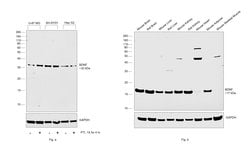

Keep as concentrated solution. Predicted reactivity: Mouse (100%), Rat (100%), Dog (100%), Cat (100%), Pig (100%), Chimpanzee (100%), Bovine (100%). Positive Control: mouse brain, rat brain, BDNF-transfected 293T. Store product as a concentrated solution. Centrifuge briefly prior to opening the vial.

| Immunohistochemistry (Frozen), Immunohistochemistry (Paraffin), Western Blot, Immunocytochemistry | |

| Human, Mouse, Rat | |